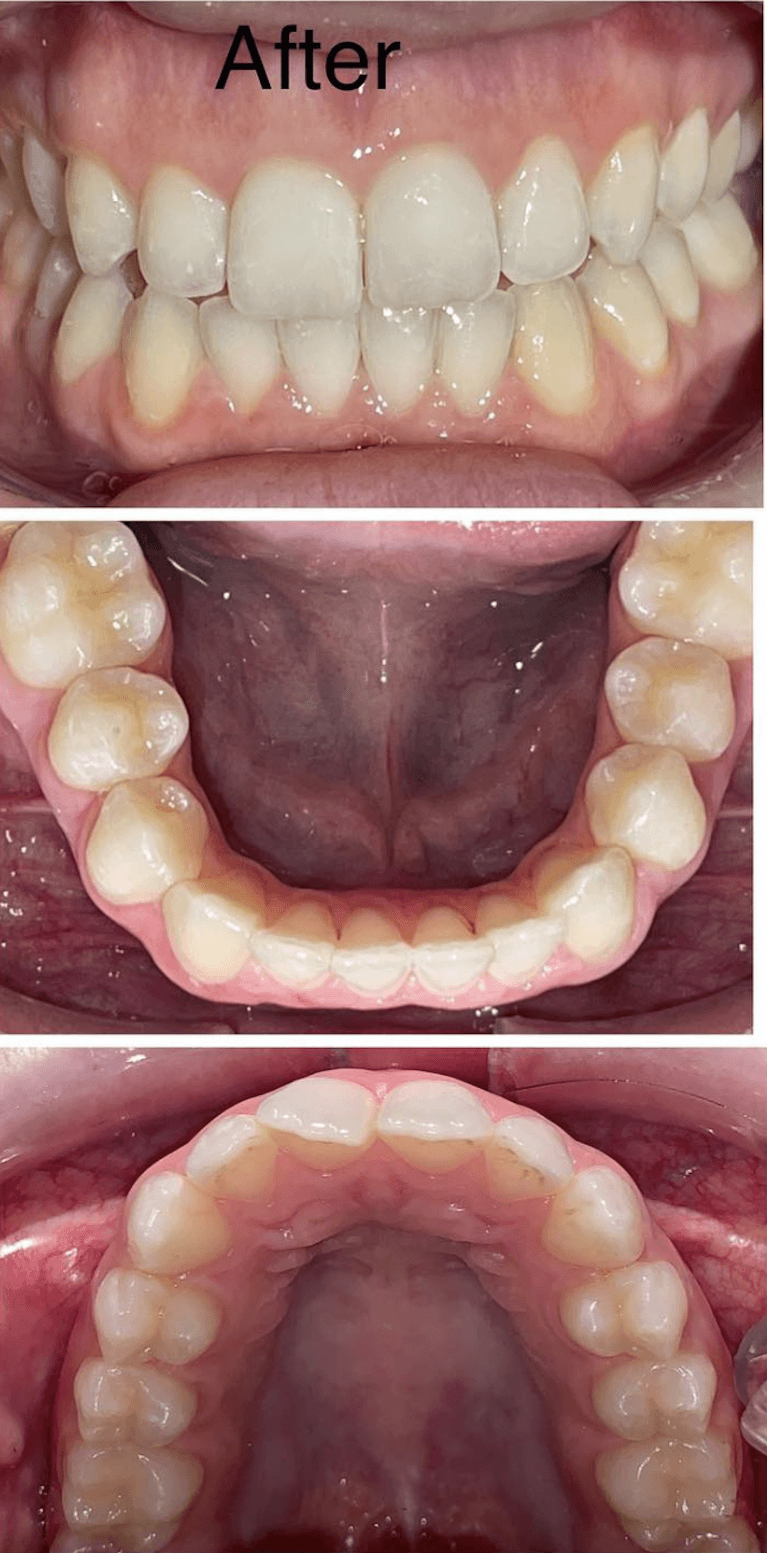

Before and after with Invisalign orthodontic treatment. Pictures taken with different phones at different setting. Used total of 27 aligners/trays. Treatment time 13.5 months